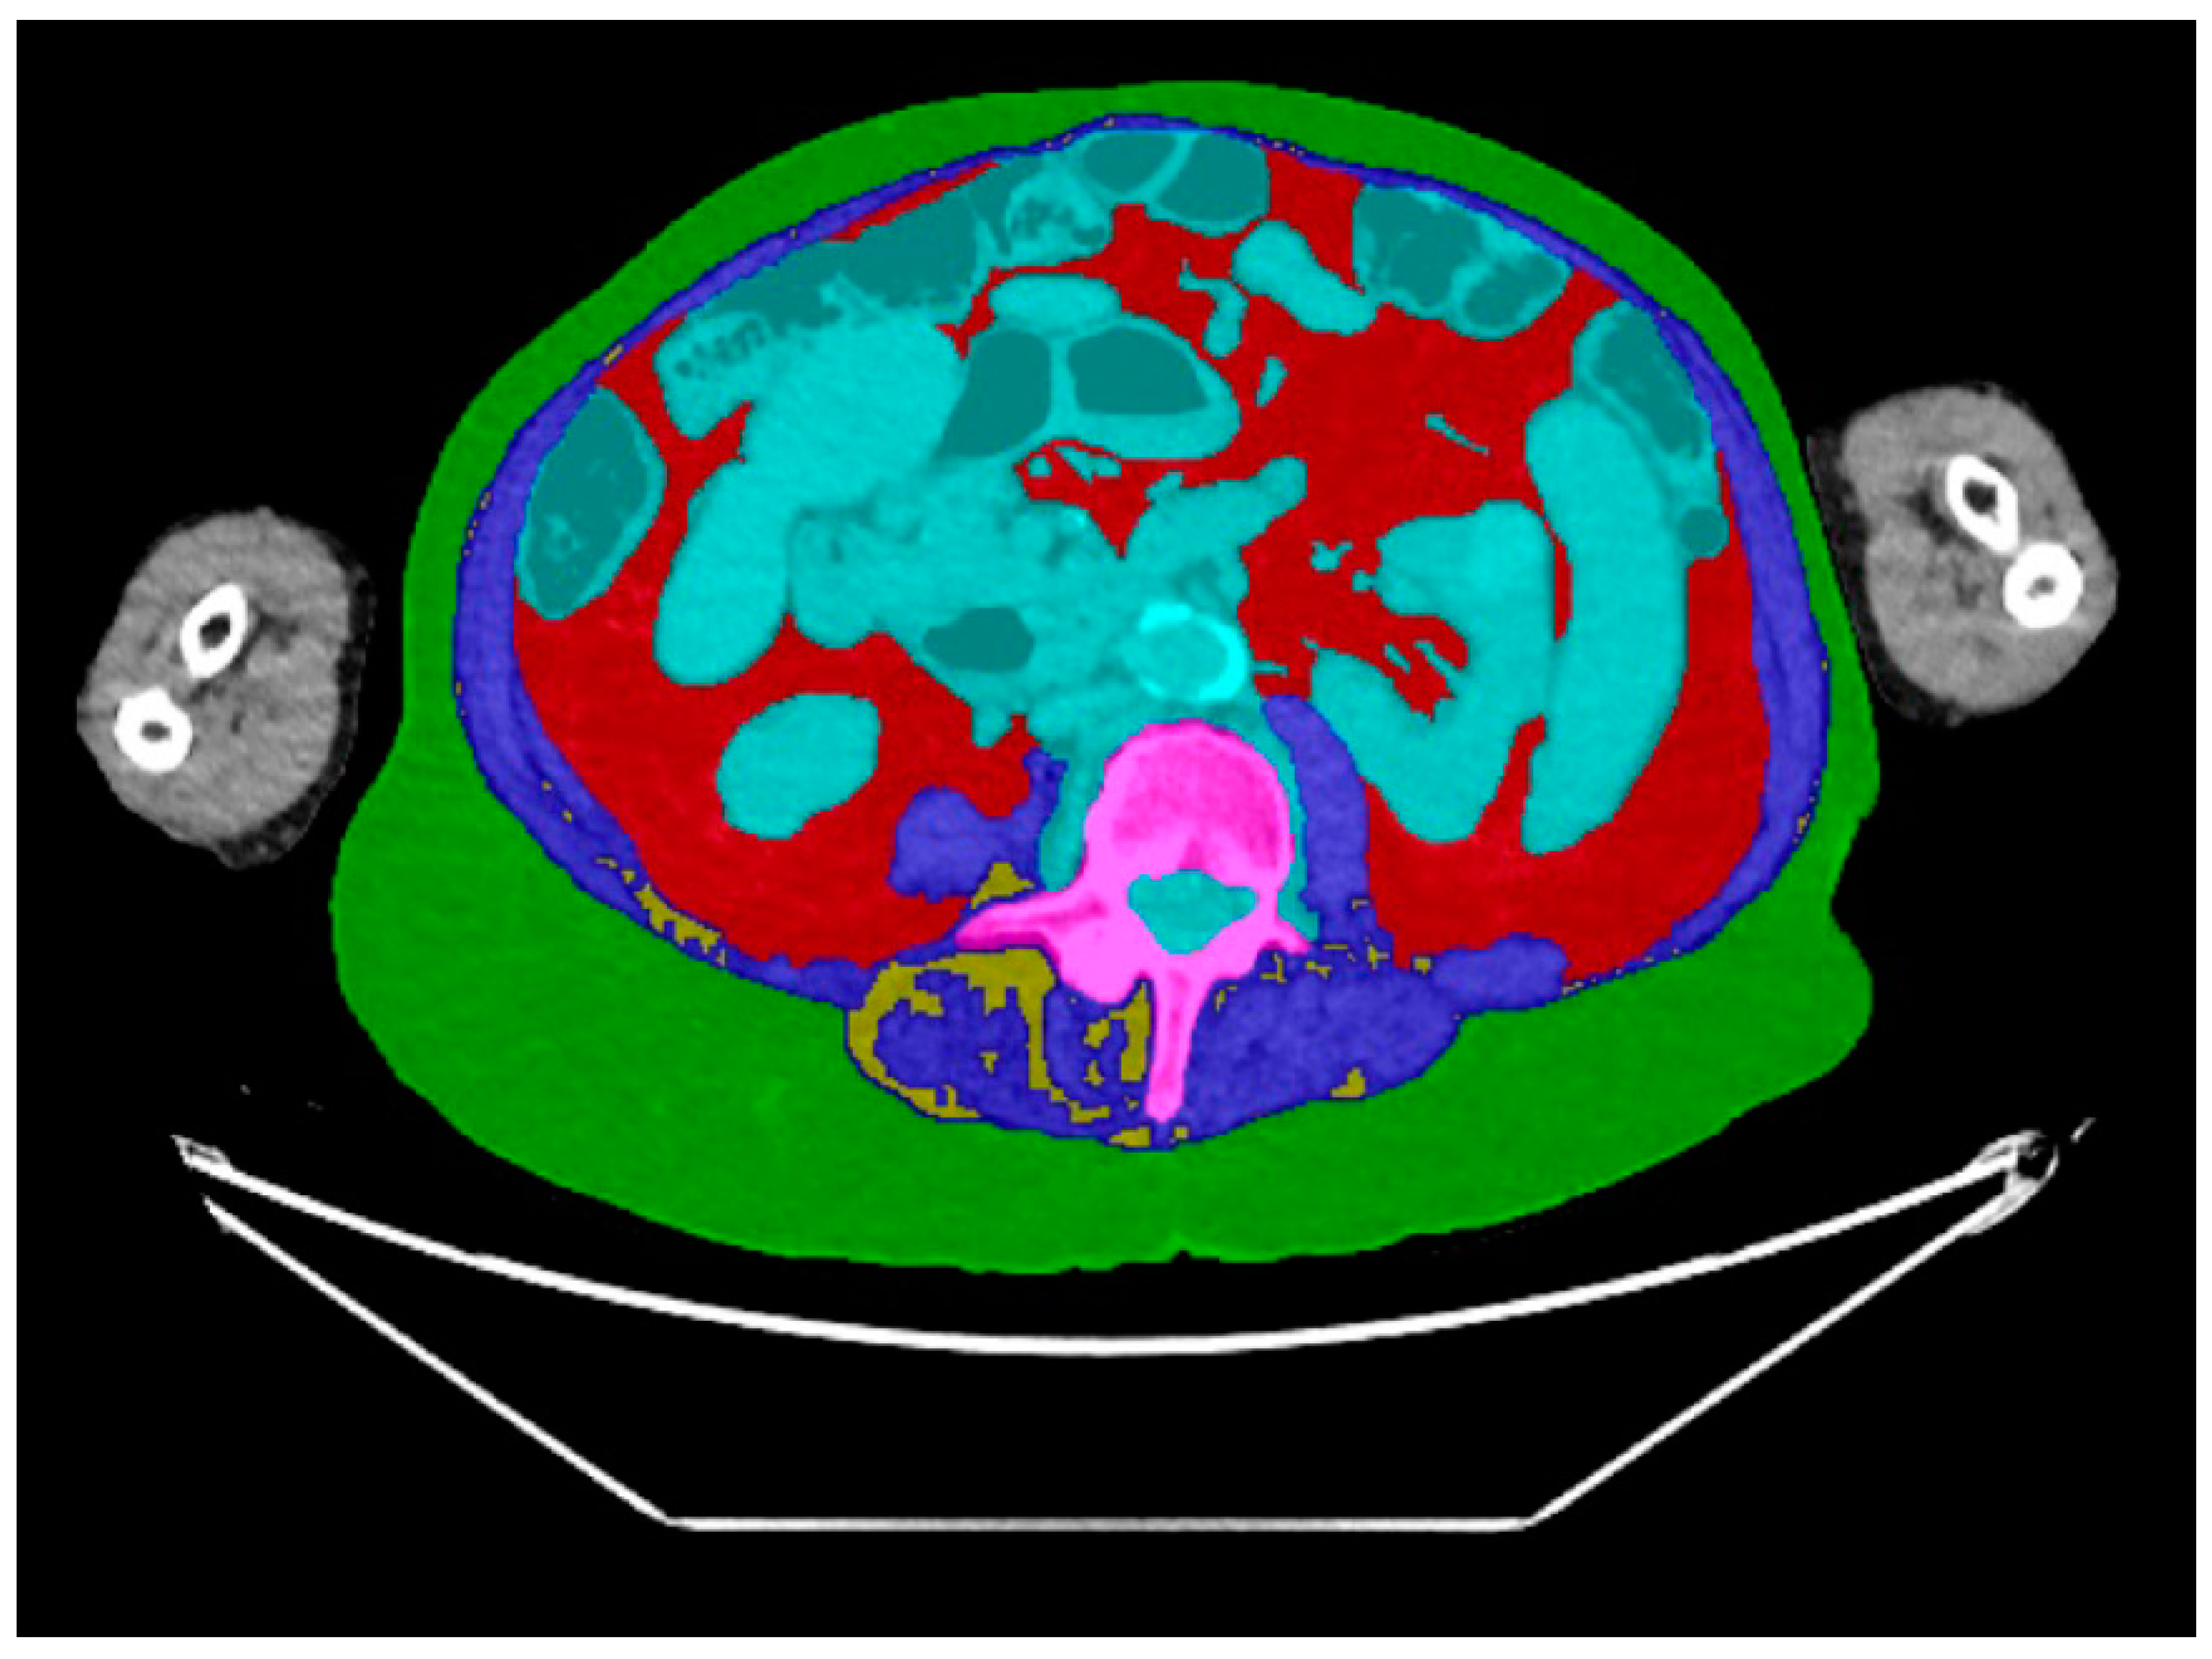

2.3. CT Body Composition Assessment

| Body composition measures a | Median (IQR) or % (n) |

| Subcutanous adipose tissue | |

| Area (cm2) | 249 (180–320) |

| Visceral adipose tissue | |

| Area (cm2) | 124 (75–211) |

| Muscle | |

| Area (cm2) | 140 (116–165) |